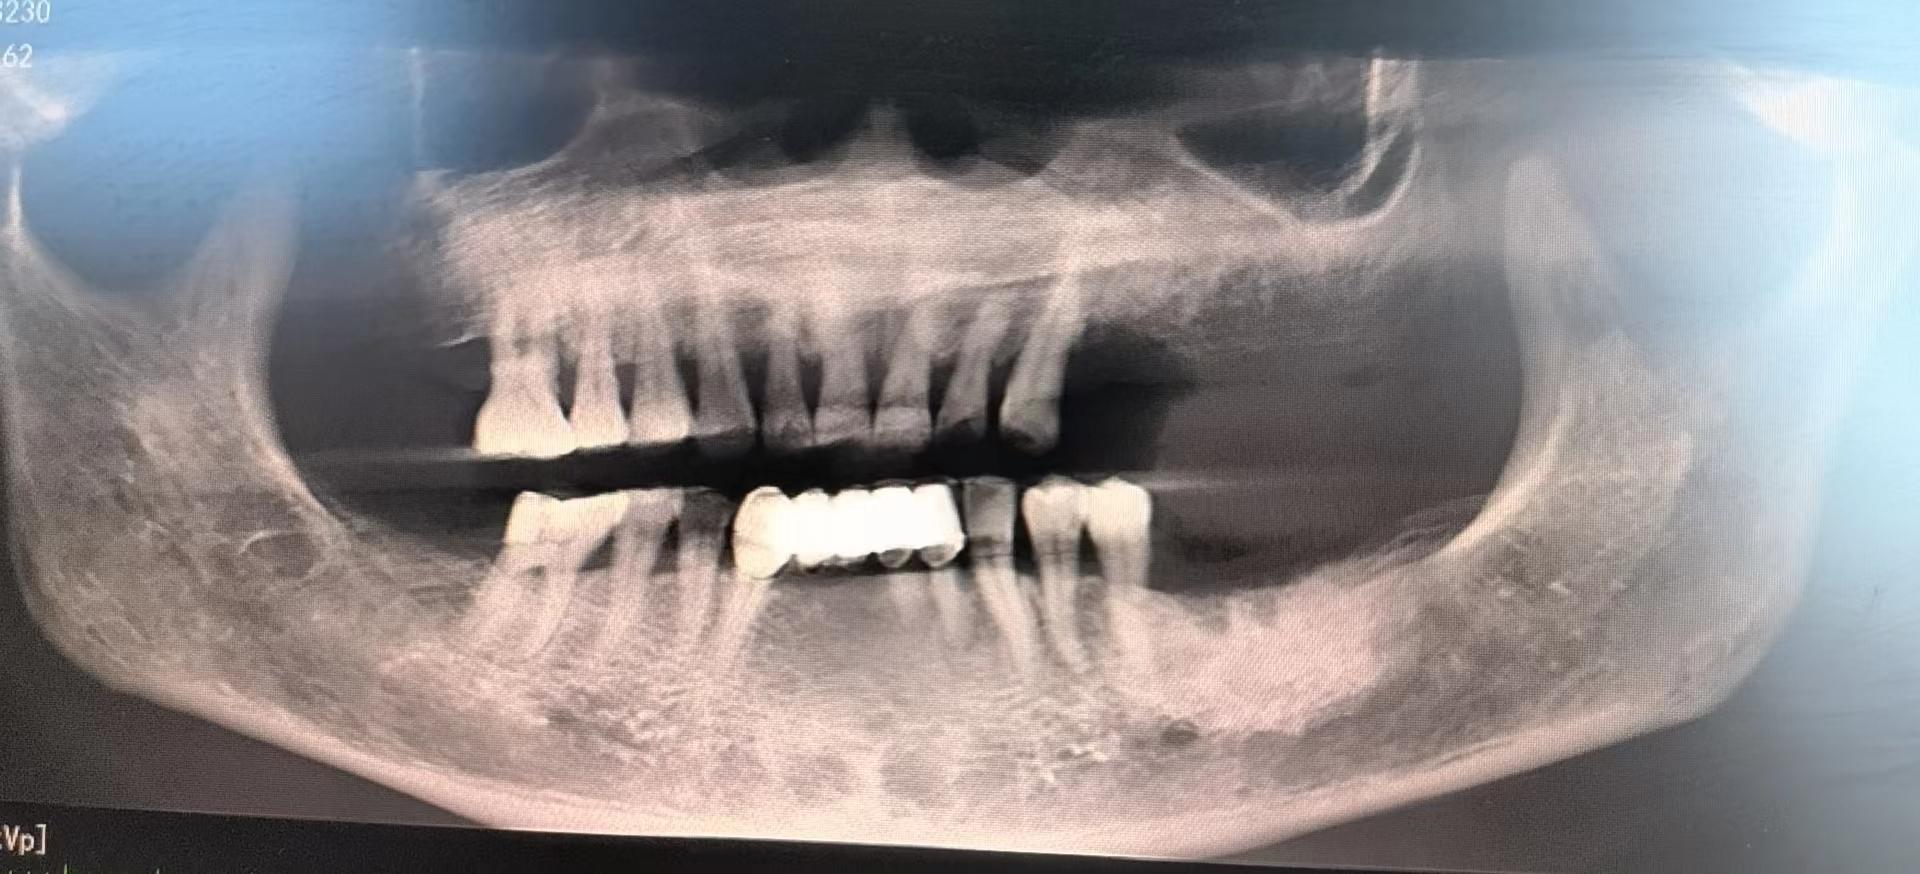

醫(yī)生檢查后,安排患者拍攝口腔CBCT,確定牙槽骨情況,并制定種植計(jì)劃,查血常規(guī),凝血功能,血壓,免疫檢查等。

為了避免患者在炎熱的夏季來回奔波,口腔科高艾玲主任團(tuán)隊(duì)決定為病人一次性種植三顆缺失的牙齒。辛璐醫(yī)生告訴患者,將通過牙科手術(shù)將人工牙根植入牙槽骨內(nèi),然后將牙齦縫合,大約10天左右拆線,之后等待骨愈合后進(jìn)行二期手術(shù)。